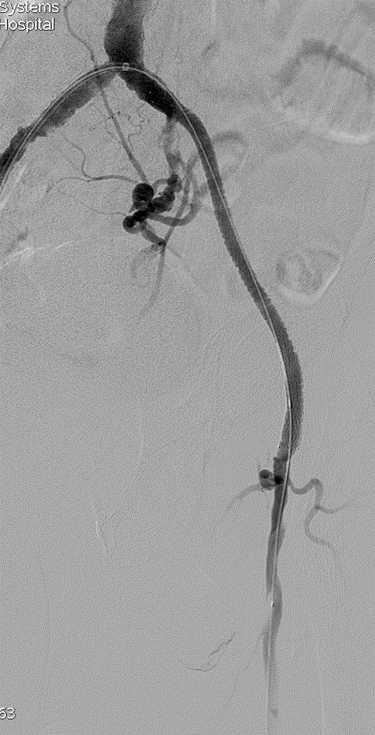

★ Case 3

左右滑动查看

★ Case 4